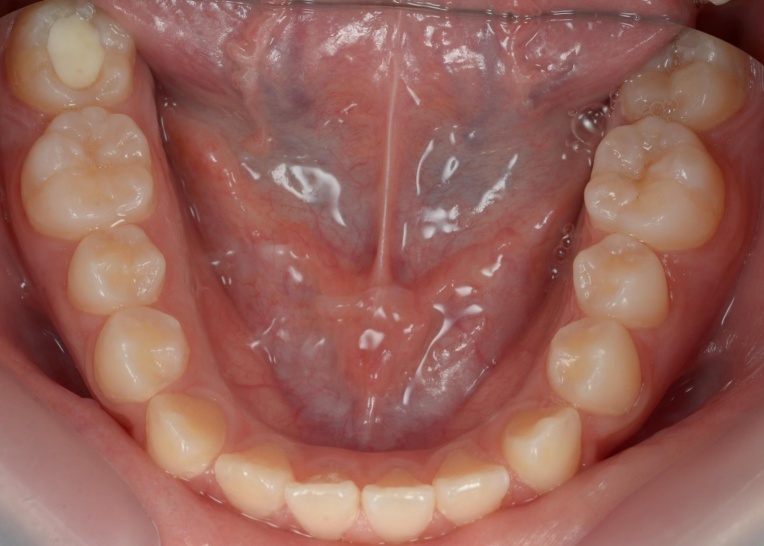

拝見したところ、重度の開咬(かいこう)が認められました。 |

見た目と噛む機能の両方を改善するため、矯正治療を提案し、同意いただきました。 |